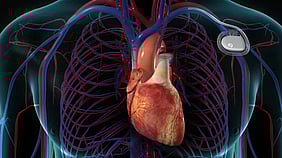

Pacemaker insertion

If your doctor has suggested that you have a pacemaker fitted, it is because you have an abnormality in the electrical conduction system of your heart. Please download our full information sheet taking you through the whole process